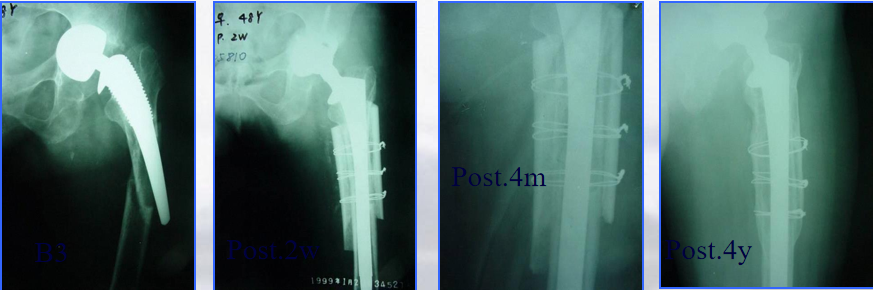

髓内固定:(二)翻修术

①适应征:假体松动的骨折

②原则:

尽可能的保留骨量

尽可能使假体与完整的宿主骨之间获得牢固固定

③假体的选择

长柄远端固定非骨水泥型

假体的长度至少要超过骨折端两倍于股骨直径的距离

骨缺损者,联合异体皮质骨板髓外固定